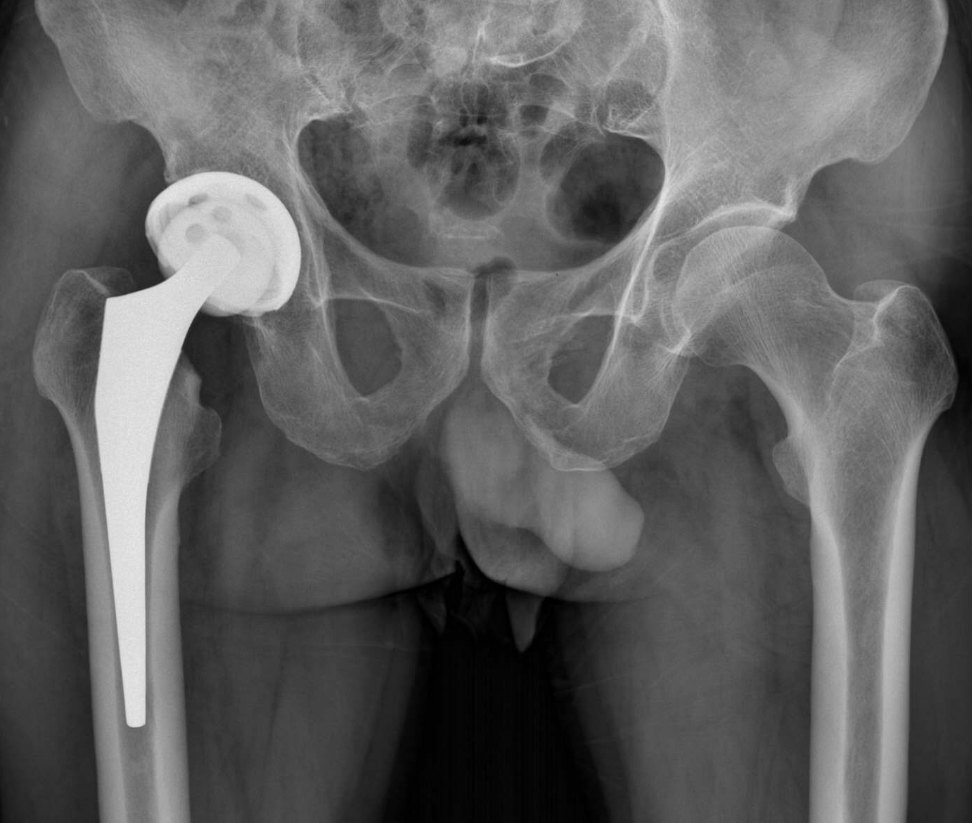

2、手術(shù)治療:對(duì)于嚴(yán)重骨頭壞死,可能需要進(jìn)行手術(shù)治療,如骨移植、關(guān)節(jié)置換等,手術(shù)治療的效果因個(gè)體情況而異,需在專(zhuān)業(yè)醫(yī)生的指導(dǎo)下進(jìn)行。